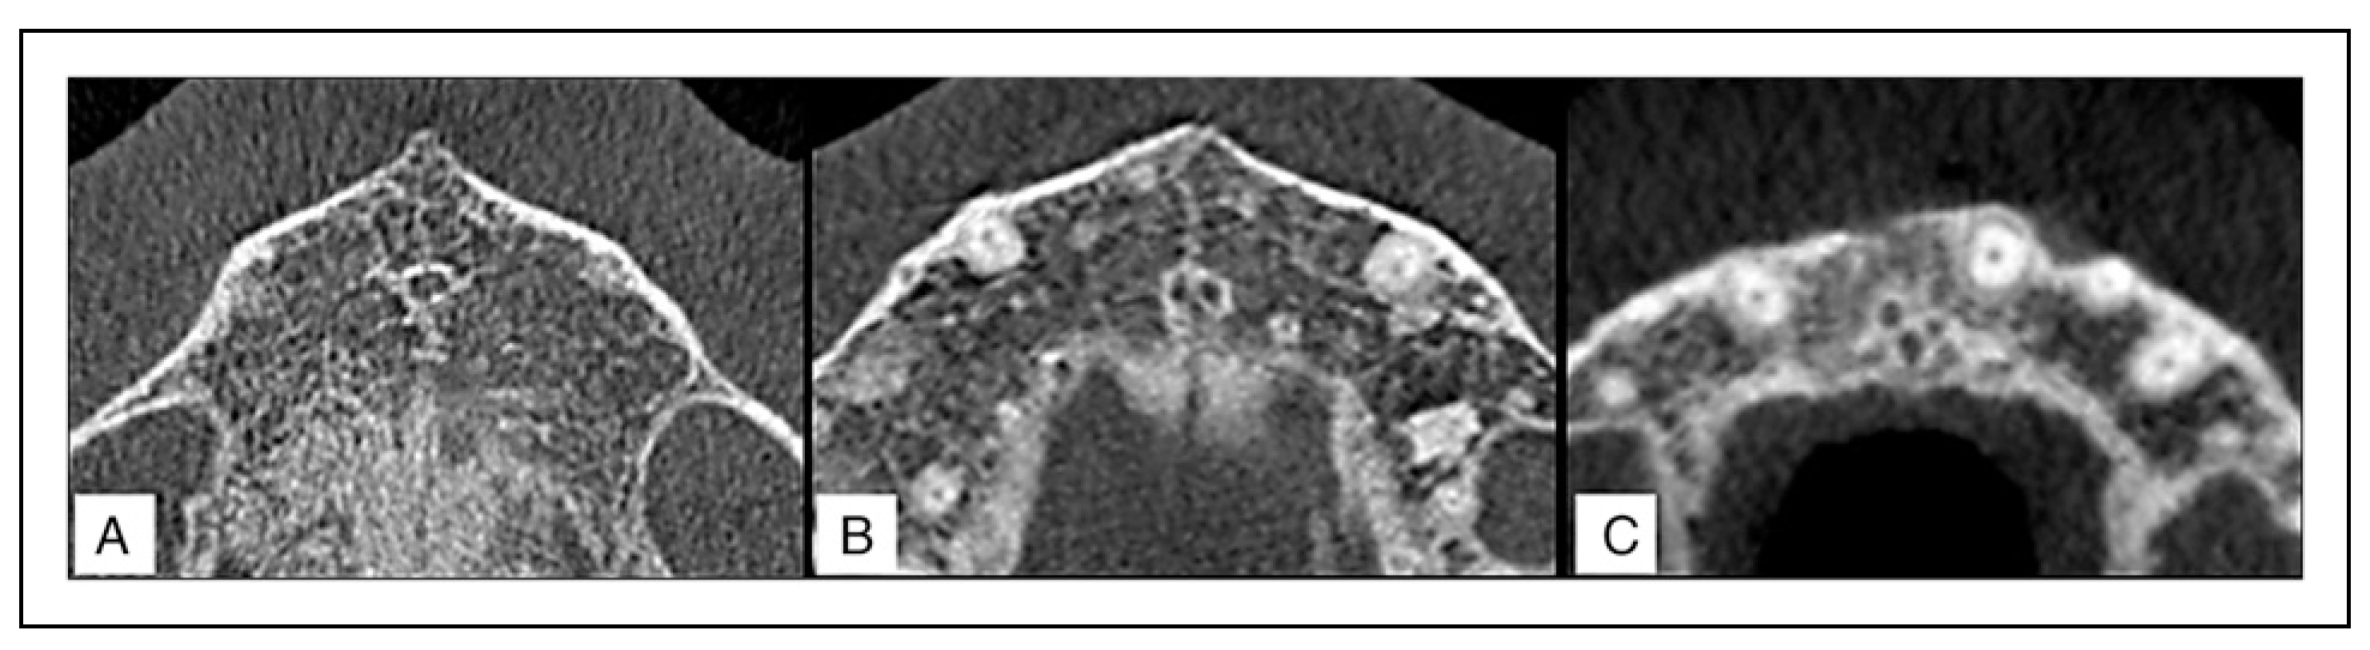

The mean length of the NPC in males was found to be 14.43 ± 3.27 mm which was significantly greater than that of the females at 11.98 ± 3.23 mm (Independent t-test, P <.05). The anteroposterior diameter of the NPC in females was greater at all 3 levels as compared to the males; conversely, the mediolateral diameter of the NPC in males was greater than that of females. These results, however, did not exhibit any sexual dimorphism (Independent t-test, P >.05). As pertains to the angulation of the NPC, the results show a similar inclination in both genders at 118° to the horizontal plane (Table 2). Two views were used in the examination of the morphology of the NPC: a sagittal view and a coronal view. In the sagittal view (Figure 3), the most common shape of the NPC for males was cylindrical followed by an hourglass, conical, banana, funnel, and tree branch patterns. On the other hand, the most common shape in females was cylindrical as well, followed by funnel, conical, banana, hourglass, and tree branch patterns. In the coronal view (Figure 4), a single canal was the most prevalent for both genders followed by the double canal for males and the Y-shaped canal for the females.

The results reveal a statistically significant difference pertaining to the shape of the NPC in both sagittal and coronal views with respect to gender (Chi-square test, P <.05).

Figure 4. Representative coronal CBCT sections of the NPC showing the various shapes encountered in the study with a clustered column bar chart showing the shape prevalence of the NPC in a coronal view for both male and female Kenyans. A combined percentage value for both genders is also depicted. (a) Single (b) Double (c) Y-shaped.